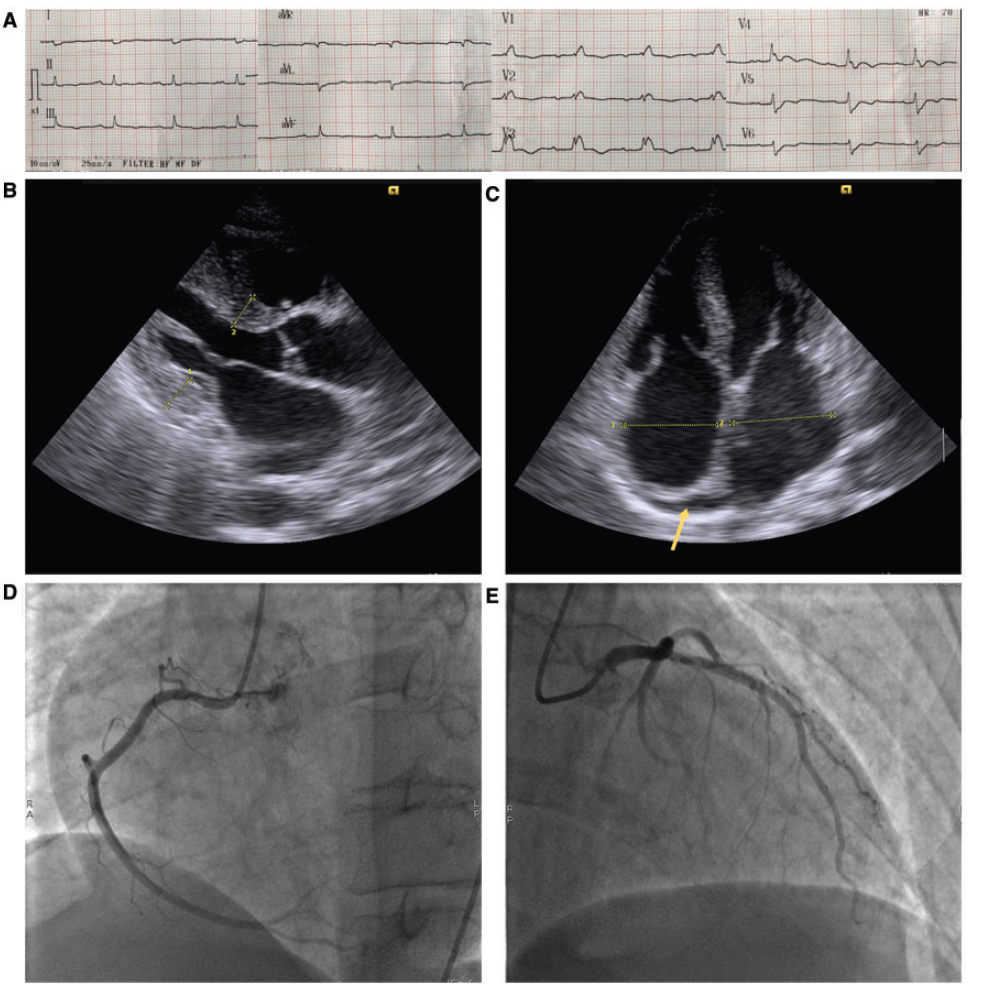

心電圖(ECG):顯示竇性心律、右束支傳導阻滯和低電壓(圖1A)。

超聲心動圖:顯示左心室向心性肥厚、雙房擴大和左心室基底低運動(圖1B和C)。

根據以上結果患者疑似為急性冠狀動脈綜合征(ACS),為進一步確認患者是否為ACS,進行冠狀動脈造影:結果顯示非阻塞性冠狀動脈(圖1D和E),此時排除ACS。

圖1 心電圖(A)、超聲心動(B和C)、冠狀動脈造影(D和E)結果